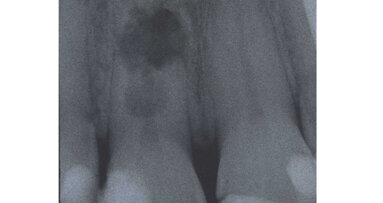

A full-mouth series of periapical radiographs was taken, and several failed composite restorations and a periapical abscess on tooth #16 were noted. Clinical examina­tion revealed a Class I dental relationship and sev­eral significant occlusal interferences. Evidence of moderate wear was found on the patient’s anterior teeth, and the patient presented with some muscular tension during a temporomandibular joint evaluation.5